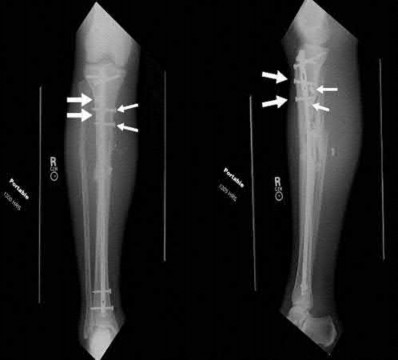

Question 6:

A 4-month-old female with developmental dysplasia of the hip (DDH) has been treated with a Pavlik harness for 4 weeks. Clinical and ultrasonographic evaluations confirm that the left hip remains persistently dislocated. What is the most appropriate next step in management?

A 40-year-old male sustains a high-energy Pilon fracture. Initial treatment consists of a spanning external fixator across the ankle joint. Which of the following clinical findings best indicates that the soft tissue envelope has recovered sufficiently to permit definitive open reduction and internal fixation (ORIF)?

Options:

- Return of the 'wrinkle sign' on the anterior ankle skin

- Epithelialization of serous fracture blisters within 48 hours

- Resolution of the dependent rubor when the leg is elevated

- A palpable dorsalis pedis pulse overriding the external fixator

- Normalization of the erythrocyte sedimentation rate (ESR)

Correct Answer: Return of the 'wrinkle sign' on the anterior ankle skin

Explanation:

In the staged management of high-energy Pilon fractures, definitive ORIF must be delayed until the soft tissue envelope has adequately healed to minimize the risk of wound complications and infection. The return of skin wrinkles (the 'wrinkle sign') indicates a significant reduction in interstitial edema and is the widely accepted clinical milestone for proceeding with definitive fixation, typically 10 to 21 days post-injury.